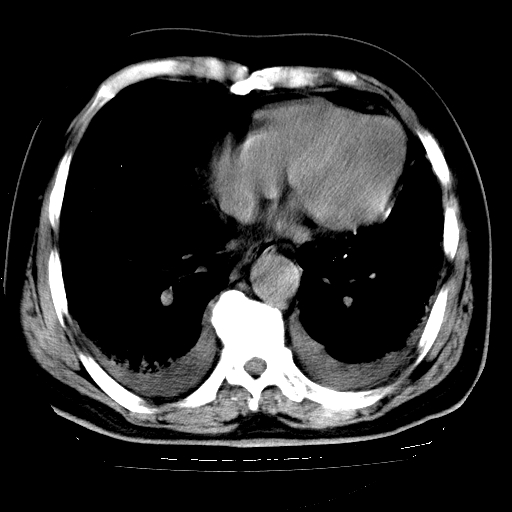

男,68岁,咳嗽、胸闷、发烧三天,查体:双肺散在湿罗音。

首先考虑特发型肺间质纤维化;两侧少量胸腔积液。

5.双侧胸腔少量积液;双侧胸膜增厚。

慢支合并感染.间质纤维化,心衰双侧少量胸腔积液

支持 慢支合并感染.间质纤维化,心衰双侧少量胸腔积液.